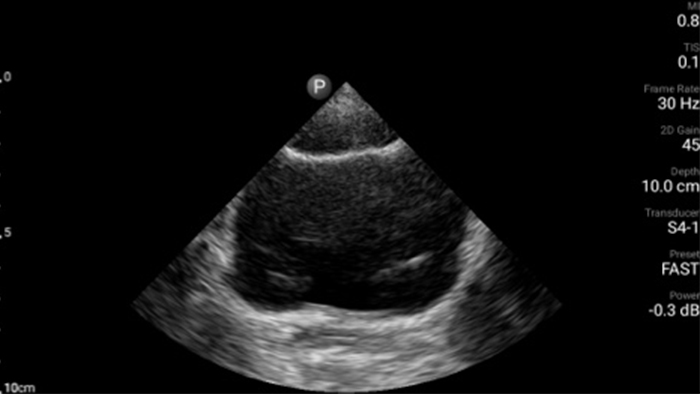

El ultrasonido portátil Lumify para anestesiología le ayuda a visualizar claramente la definición de los bordes con la colocación de la aguja, los nervios circundantes, los vasos sanguíneos y los planos fasciales.

• Rango extendido de frecuencias de operación de 4 a 1 MHz • 2D, Doppler a color, Modalidad M, XRES avanzado e imágenes armónicas multivariables • Imagenología de alta resolución para aplicaciones abdominales y cardíacas: optimizaciones de preajustes de imágenes cardíacas, gineco-obstétricas, pulmonares, abdominales y FAST.

Desde revelar los detalles sutiles de una imagen hasta descubrir la definición del tejido enriquecido desde múltiples ángulos, Lumify puede ayudarlo a tomar decisiones en tiempo real con más confianza desde la evaluación hasta la recuperación.